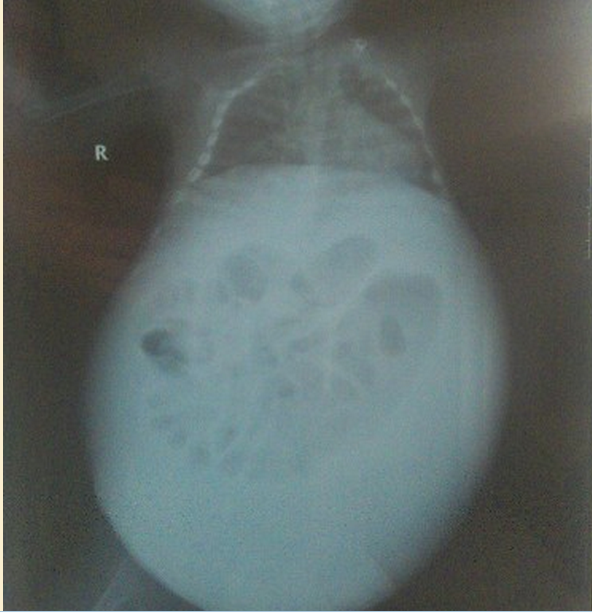

来自山东德州市陵县神头镇南于村的男婴康瑞博,出生于2012年6月6日。孩子在2个多月的时候开始不适,当时没有在意,5个多月的时候肚子开始慢慢胀大,父母到处寻医问药化了2万多,但仍然不见效。目前男婴康瑞博肚大如鼓,肚皮上血管暴露突起,一家人带着孩子在北京先后去过协和医院、北京儿童医院、解放军二炮医院等医院,但因各种原因均未能得到明确诊断,孩子体质虚弱呼吸困难十分痛苦,肚子上爬满的血管粗大曝起。2013年2月17日住院求治于解放军军区总医院八一儿童医院,专家在治疗孩子的肺炎的同时,已开始进行各类详细检查,尽快进入针对性治疗状态。

今日下午得到外科主治医生的最新病情反馈:孩子腹水化验及检查结果已出,基本判断是属于乳糜腹疾病。肢体淋巴水肿也是由此引起,现肺炎很严重呼吸困难。昨日已抽出腹水200毫升,先施予保守治疗,开始禁食及静脉营养。看破裂乳糜管能否自行长好,再观察是否要手术缝扎。乳糜腹病是腹腔内淋巴系统中的乳糜液异常漏出,导致腹腔内乳糜液积聚引起大肚子。发病原因复杂,属先天性发育障碍也可能是创伤所致。小瑞博被判断是乳糜管破裂,导致的乳糜微粒形式进入淋巴管和液体进腹腔。乳糜液含丰富营养,长时间大量流失将引发机体低蛋白血症并易继发细菌感染。 小瑞博目前病情紧迫,此病治疗时间又长。加上肺炎的治疗,总体判断评估,治疗预算为8万左右。为了尽快控制住病情,急需社会爱心力量的一起努力。